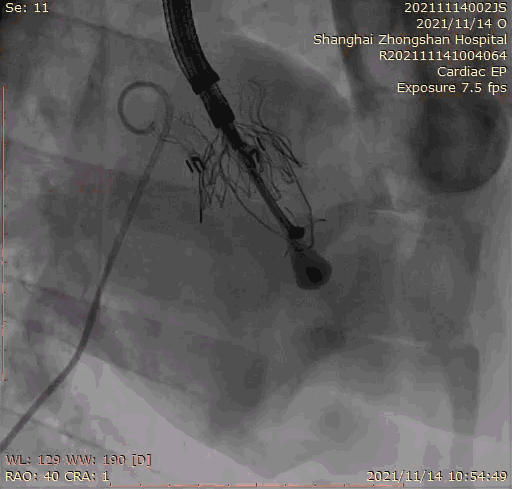

本次臨床前研究經(jīng)右側頸靜脈置入LuX-Valve Plus輸送系統(tǒng)可調彎鞘管,在DSA及超聲引導下將人工三尖瓣瓣膜植入到原有三尖瓣位置,利用獨特的錨定技術將人工瓣膜支架可靠固定在預定的位置。